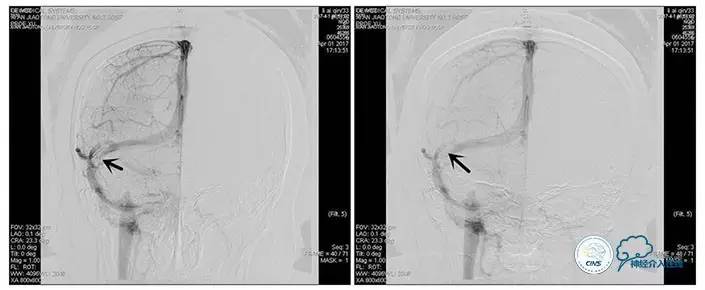

术中造影

5ml/s,总量8ml,压力100~150

术后造影

术毕远近端压力差为:0

术中测压

远端压力:530mmH2O

近端压力:120mmH2O

狭窄较前有改善

术中测压:

远端:520mmH2O,

近端:190mmH2O。

术后远、近端压力差为:0